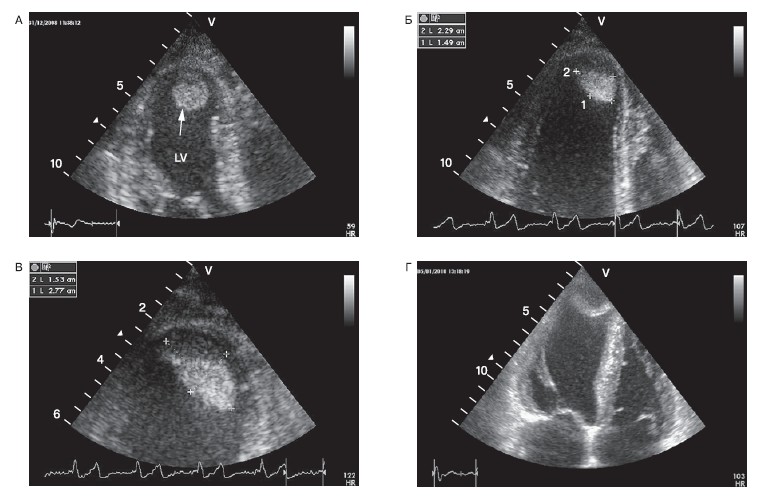

Это нередко приводит к типичному сценарию у таких больных с неоднократной их госпитализацией в стационар с подозрением на развитие ИМ при всяком обращении за медицинской помощью по поводу возникновения болей в грудной клетке. В итоге при расспросе пациент указывает на якобы перенесенные им множественные ИМ, которых может быть до 5—10 и более. При ЭхоКГ у таких больных выявляется выраженная асимметричная гипертрофия межжелудочковой перегородки (МЖП) ЛЖ небольших размеров. Эти изменения нередко сопровождаются динамической обструкцией выносящего тракта ЛЖ с характерными для нее движениями створок митрального (переднесистолическое движение створок митрального клапана — МК к МЖП) и аортального клапанов (среднесистолическое прикрытие створок аортального клапана) (рис. 2).

Рисунок 2. Выраженная эксцентричная гипертрофия левого желудочка с толщиной межжелудочковой перегородки 2,8 см у больного с гипертрофической кардиомиопатией.

Подобная картина ЭхоКГ и отсутствие типичной динамики на ЭКГ позволяют установить диагноз ГКМП. Следует отметить, что у больных с ГКМП при ЭхоКГ могут быть выявлены НЛС в зонах миокарда, соответствующих выраженной гипертрофии, обычно в базальных и средних отделах МЖП. Подобные НЛС обычно не свидетельствуют в пользу ИМ, а обусловлены относительной гипокинезией значительно гипертрофированного миокарда. Выявляемые при этом зоны нарушенной сократимости в большей степени соответствуют локализации значительно гипертрофированного миокарда, а не стандартным зонам его коронарного кровоснабжения.